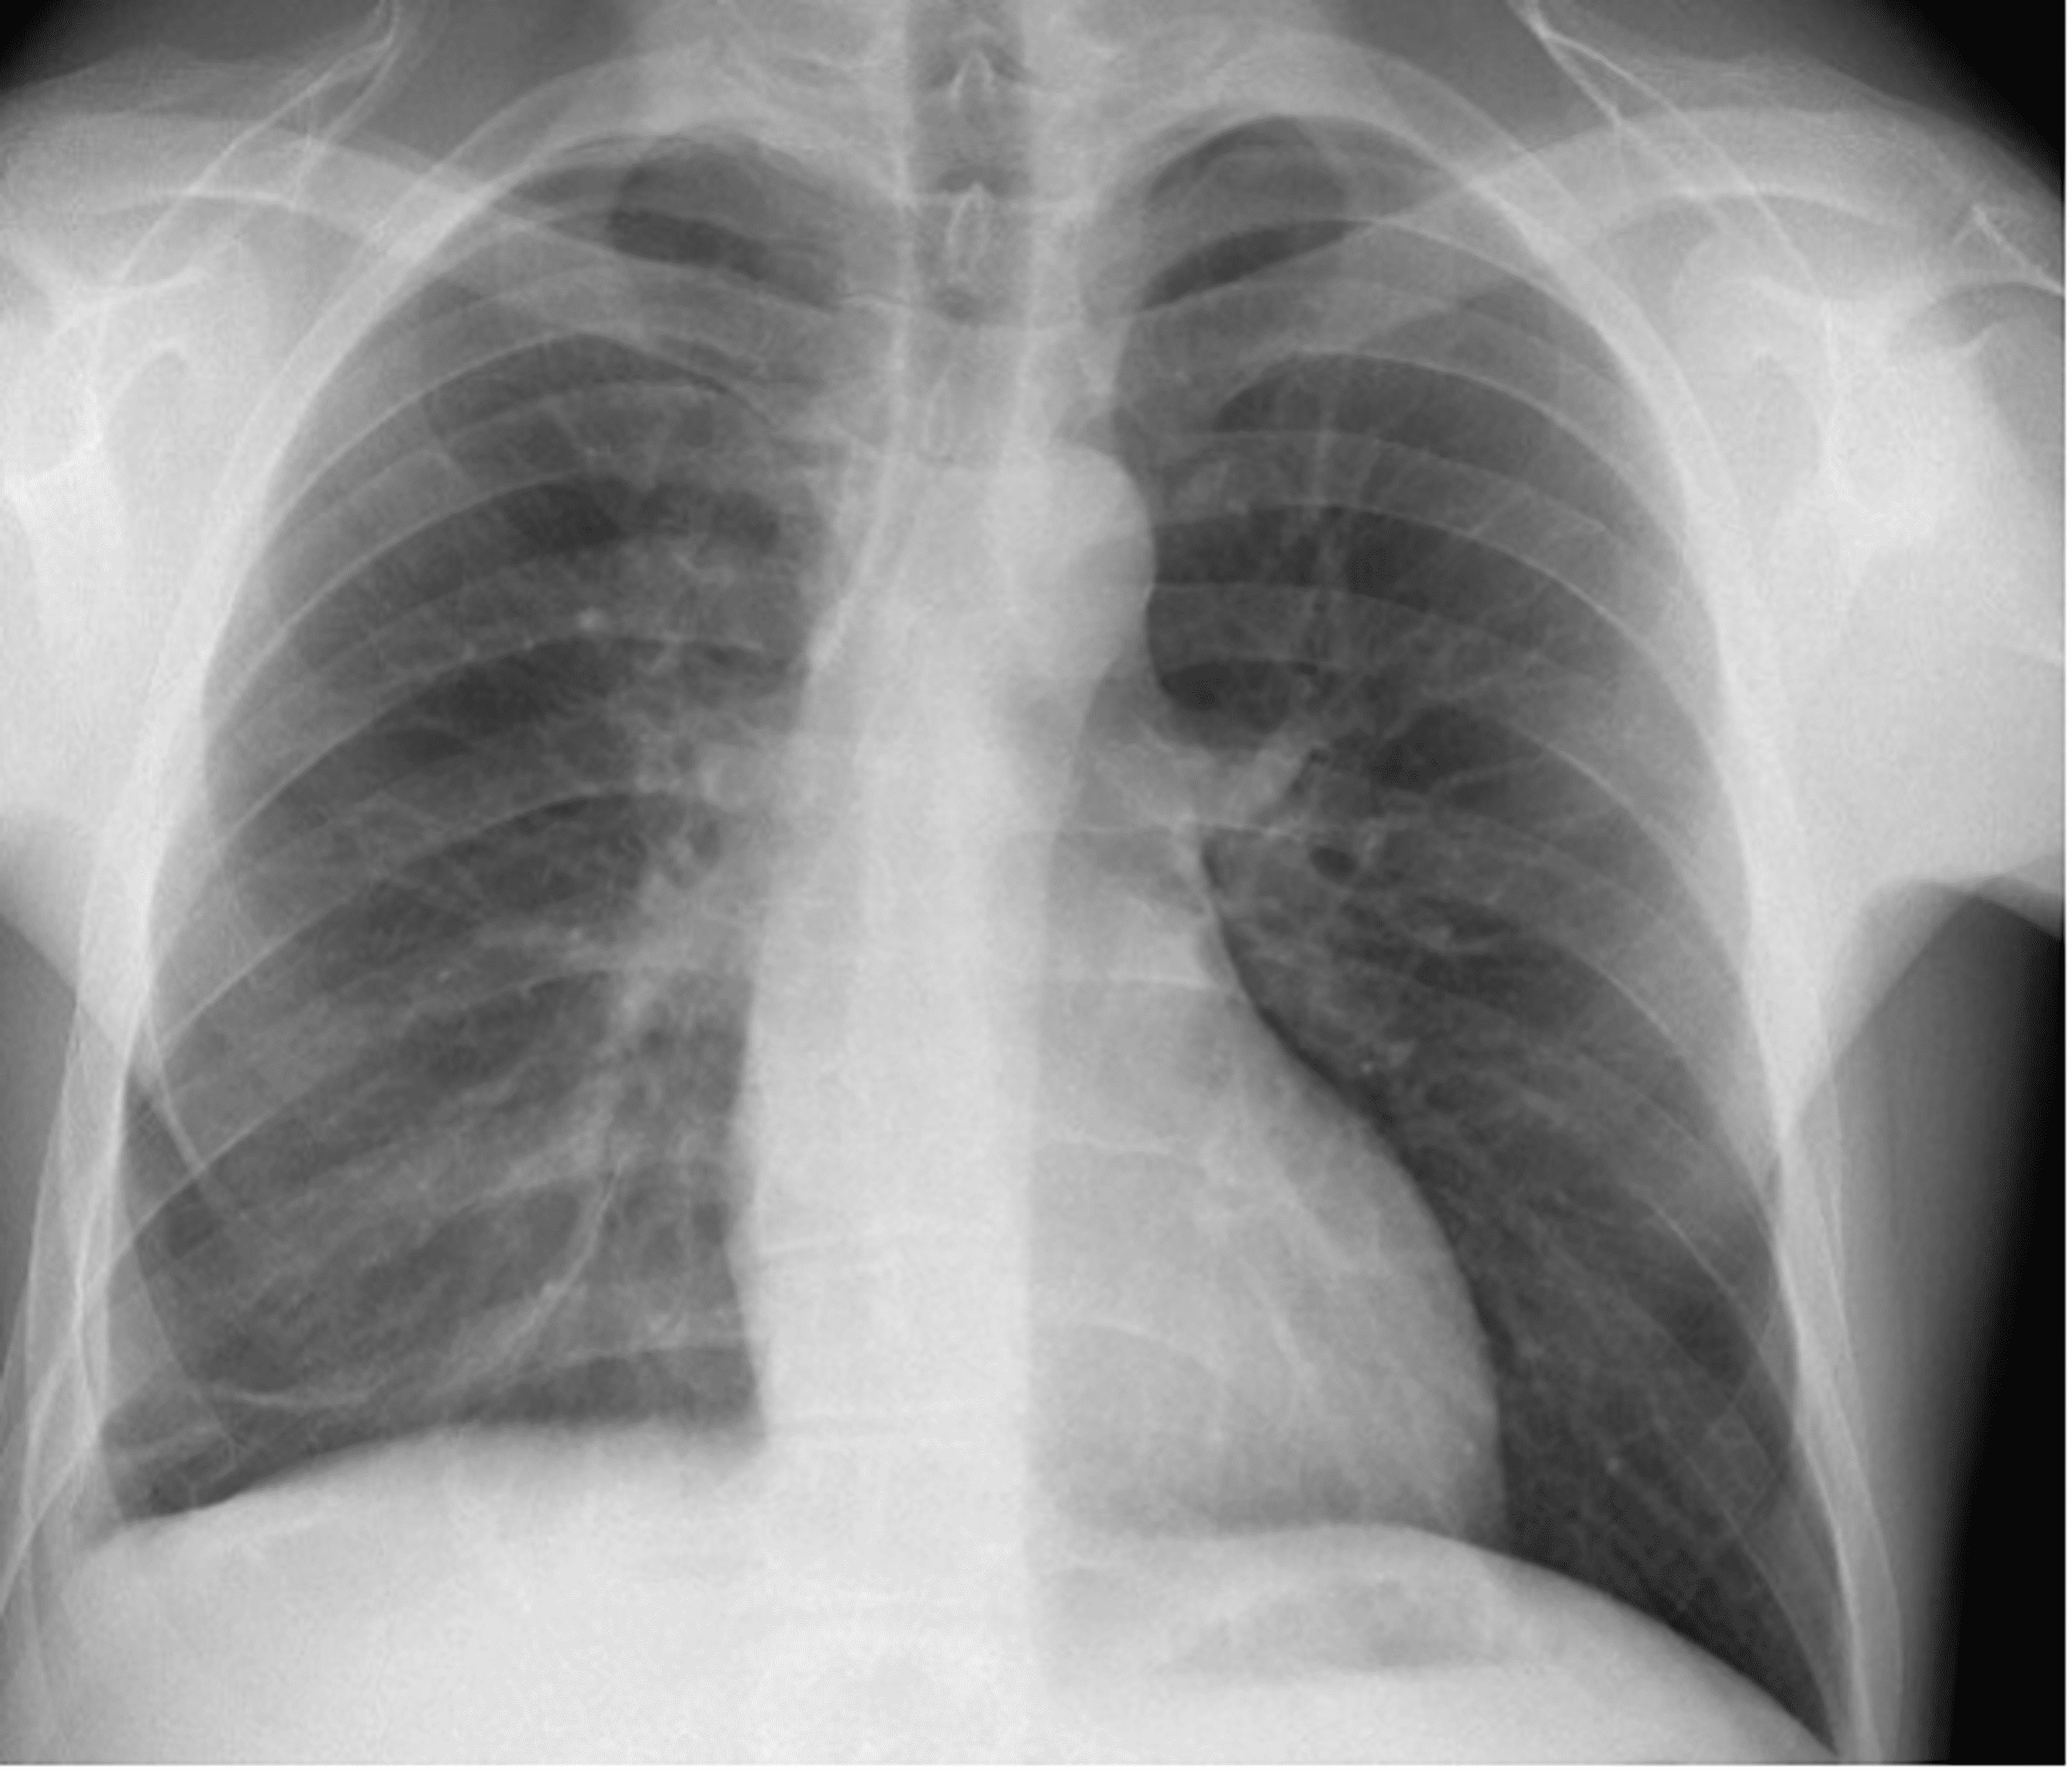

Ultimately, a respiratory review was warranted given the patient’s history with pulmonary sarcoidosis and a thorough evaluation sought the need for multiple investigations including a CT sinus, CT thorax, and bronchoalveolar lavage to investigate a preliminary diagnosis of EGPA. In addition, he was commenced on 500 mg of IV methylprednisolone on a once-daily basis for three days followed by a weaning course of prednisolone starting at 60 mg and Septrin as prophylaxis. CT thorax revealed small bilateral pleural effusions, bibasal atelectasis, slightly prominent bilateral hilar, and perihilar lymphadenopathy consistent with sarcoidosis, and a very large 3 cm pericardial effusion, which warranted urgent cardiothoracic input. The patient was thereby admitted to the coronary care unit and started on colchicine. Pericardiocentesis was not performed given the posterior location of the effusion and a cardiac MRI was booked to investigate for any fibrosis/sarcoid following resolution of the effusion. CT sinus revealed a hypoplastic left maxillary sinus with longstanding opacification and bronchoalveolar lavage fluid was shown to have >5% eosinophils. The patient had 22 chest X-rays and three CT thorax scans performed from 2014 to 2022. All chest radiology was reviewed to identify any evidence of migratory infiltrates. Temporal proof showing infiltrates being migratory was identified (Figures 8, 9) with the addition of altering small pleural effusions seen bilaterally (a feature that is evident in 50% of patients with EGPA) [6].